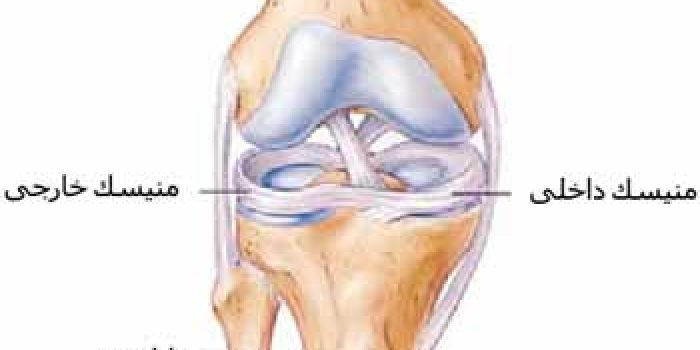

ساختمان زانو

پارگی منیسک

معمولا به علت چرخش ناگهانی ران روی ساق یا ایستادن ناگهانی هنگام دویدن یا تکل خوردن در حین فوتبال ایجاد میشود.